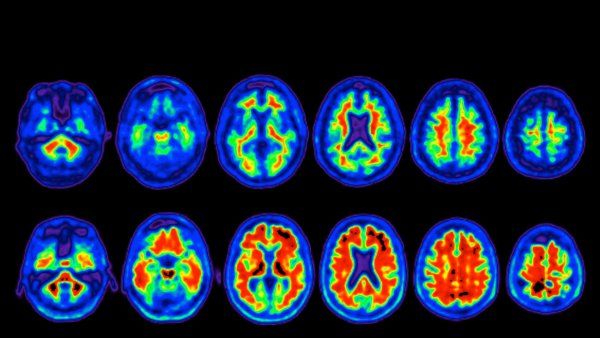

PET scan of a brain

Alzheimer’s and Dementia

Many believe dementia — a set of symptoms characterized by significant, inhibitory cognitive decline — is a normal side effect of aging. That said, while over 9.9 million new cases occur every year around the world, the onset of dementia is not inherent to the process of aging.

UCSF researchers are delving into the biomechanical and neurological processes that might contribute to the prevalence of this condition as we grow older. One day it may be possible to prevent the progression of diseases like Alzheimer’s, helping individuals live fuller lives.